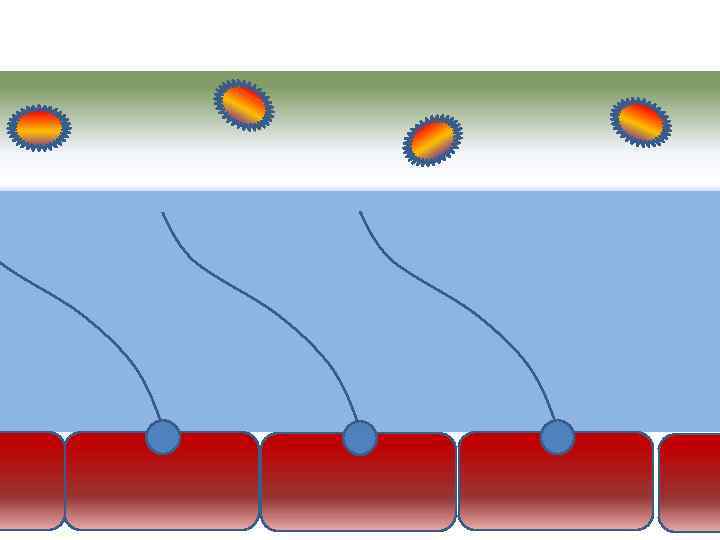

Движение клеток реснитчатого эпителия Движение вперед 1 – 3 Обратное движение 4 – 8

Движение клеток реснитчатого эпителия Движение вперед 1 – 3 Обратное движение 4 – 8

Механизм защиты легкого Слизь (зеленый цвет) нейтрализует и связывает патогенную флору(синий цвет) Слизь – это барьер между клетками и патогенной флорой Слизь – это транспортное средство

Механизм защиты легкого Слизь (зеленый цвет) нейтрализует и связывает патогенную флору(синий цвет) Слизь – это барьер между клетками и патогенной флорой Слизь – это транспортное средство